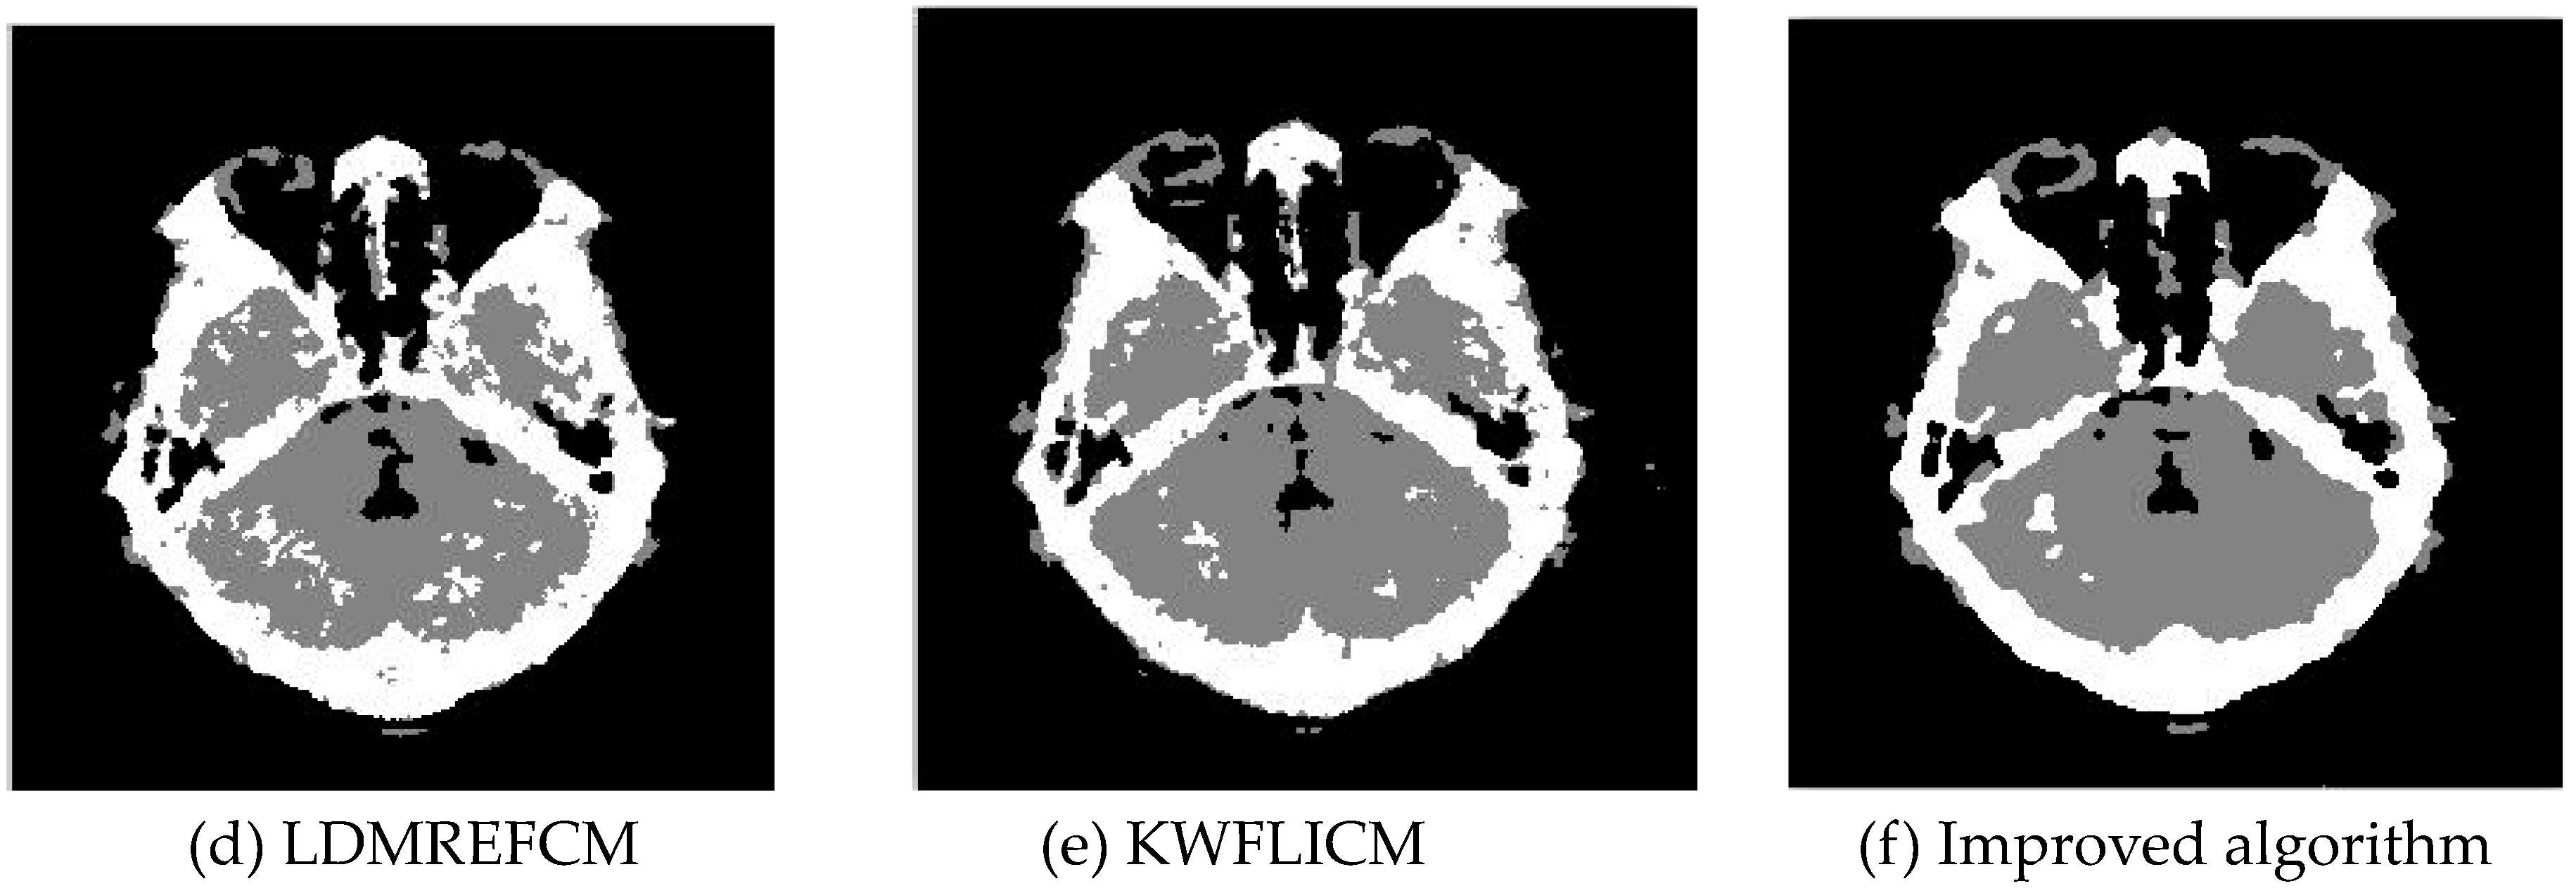

Gaussian noise was added to two remote sensing images with a mean value of 0 and mean variances of 57 and 80. Gaussian noise was added to images containing four artificial categories, brain CT (Computed Tomography) images, and camera images with a mean value of 0 and mean variances of 140 and 161. The number of clusters was set to 3, 4, 2, and 2. The results were compared using the results from the FLICM, FCM_S, LDMREFCM, and KWFLICM algorithms and the improved algorithm. The original image is shown in Figure 1, and the experimental results are shown in Figure 2, Figure 3, Figure 4 and Figure 5 (b–f). The error rate and PSNR of the segmentation results are shown in Table 1 and Table 2, and the iteration time and the number of iterations are shown in Table 3 [40,41].

3.1.2. Test Result

Comparing the segmentation results of the five algorithms in Figure 2, Figure 3, Figure 4 and Figure 5 for four images with different degrees of Gaussian noise interference, we can see that the segmentation results of the FCM_S, FLICM, and LDMREFCM algorithms still contained many noise points; the KWFLICM algorithm contained fewer noise points; while the improved algorithm has the fewest noise points. Table 1 shows that the improved algorithm had the highest signal-to-noise ratio compared with the other four algorithms, which shows that the improved algorithm had the strongest anti-Gaussian noise ability. Table 2 shows that the segmentation result of the improved algorithm was the smallest of all the algorithms, which shows that the segmentation result of the improved algorithm was closer to the ideal segmentation result and had a better segmentation performance. Comparing the PSNR and iteration time of each algorithm in Table 3, the average PSNR of the improved algorithm was 0.7 dB higher than that of the KWFLICM algorithm, and the average iteration time of the improved algorithm was 500 s less than that of the KWFLICM algorithm [42,43]. The iteration times of the FCM_S and FLICM algorithms were the lowest, but the difference between the improved algorithm results and the PSNR was 2–5 dB. The anti-noise ability of the FLCM and FCM_S method was poor. Combining the PSNR test results and the iteration time, the improved algorithm had a better anti-Gaussian noise segmentation performance.

Figure 4. Gaussian noise interfering with the brain slice image (a) and the segmentation results (bf).

Sensors 20 02391 g004